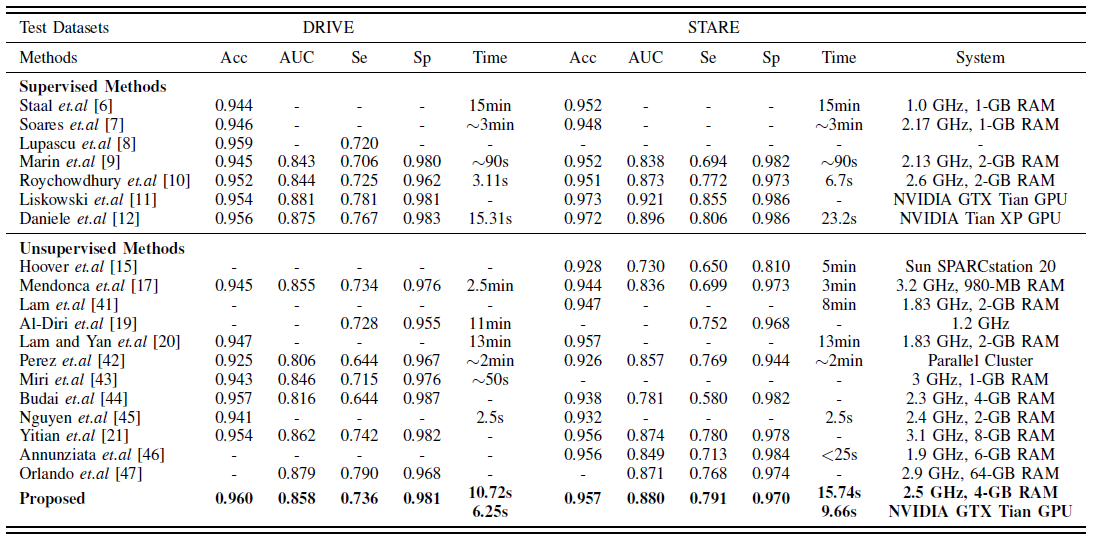

图五 分层更新的示例流程图 本文通过与多个血管分割算法进行比较验证了所提算法的有效性,对比结果如图六所示。实验结果表明,基于分层抠图模型的血管分割算法在两个公开的数据库: DRIVE和STARE上均取得了较好的分割结果。下面我们给出一些血管分割的实例对比结果(如图七所示)。在图七的(a)(b)(c)(d)中,左图均为医生分割的结果,右图为基于算法所分割出的结果。不难看出,基于该算法所得到的分割结果,相比医生分割的结果,提取了更多复杂的特征信息。

图六 算法对比实验结果